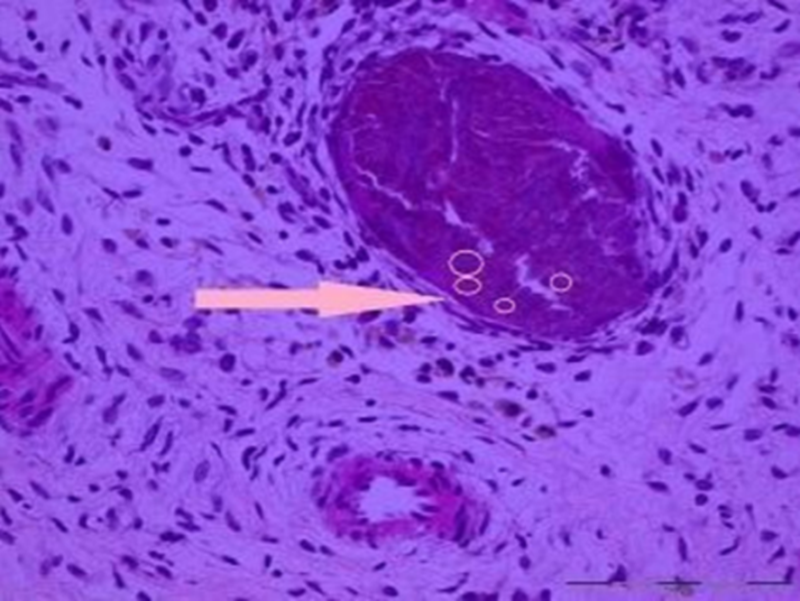

该病诊断的金标准:关节滑液中发现CPPD结晶。

图4.膜组织内见多灶、团块状紫蓝色钙化结晶体沉积

偏振光下正双折射菱形晶体